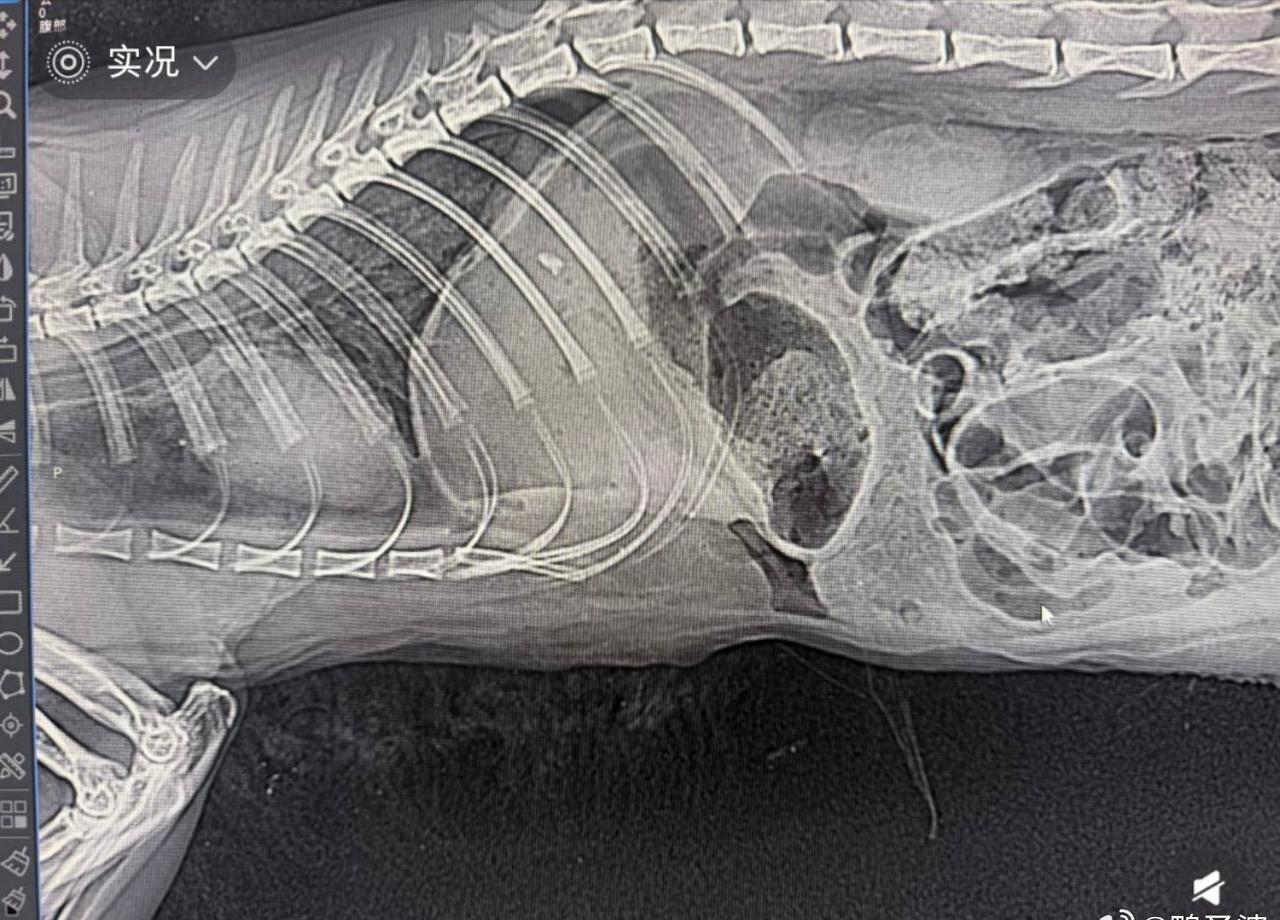

- “拍了片子,腹部全是空的,硬生生被饿了6天,然后袋子套着头,窒息死的,饿死

- “拍了片子,腹部全是空的,硬生生被饿了6天,然后袋子套着头,窒息死的,饿死的!” 看到这里真的绷不住…[流泪] ​​​